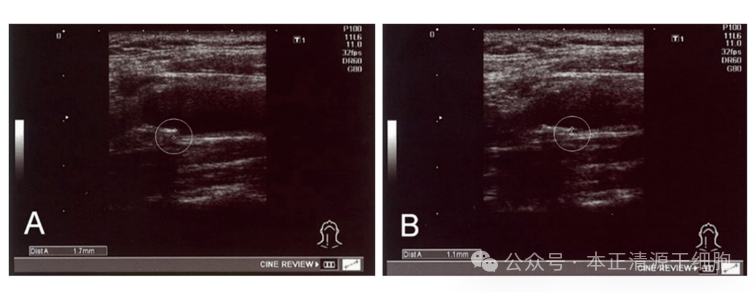

18 例治疗前IMT值异常的患者, 治疗后 IMT 值显着下降(p < 0.01)。其中,一名 56 岁男性患者在MSCs治疗前 ( a ) 和治疗后 ( b ) 的颈总动脉 IMT 示例显示,治疗后近 4 个月,IMT 从 1.7 毫米下降至 1.1 毫米

IMT:颈动脉内膜中层厚度;目前认为正常IMT值应小于1.0毫米,IMT在1.0至1.2毫米之间为内膜增厚,1.2至1.4毫米之间为斑块形成,IMT大于1.4毫米为颈动脉狭窄。